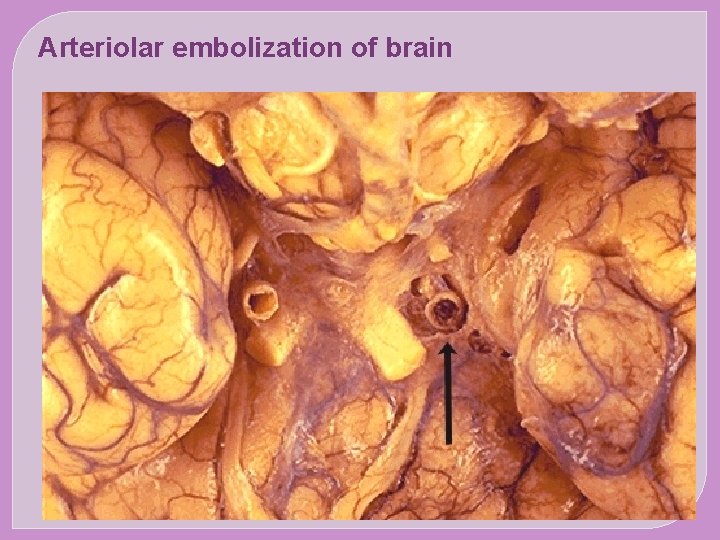

SYSTEMIC EMBOLISM The origin of emboli: Most arise from intracardiac mural thrombi or from ulcerated atherosclerotic plaques The sequel: Arteriolar embolization (e. g. the brain, kidneys , spleen and intesrines)

Arteriolar embolization of brain